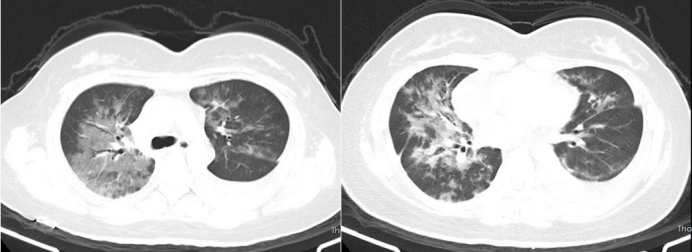

• 肺部CT2025年2月27日):双肺磨玻璃样间质改变(图1)

图片

1  入院后患者肺部CT